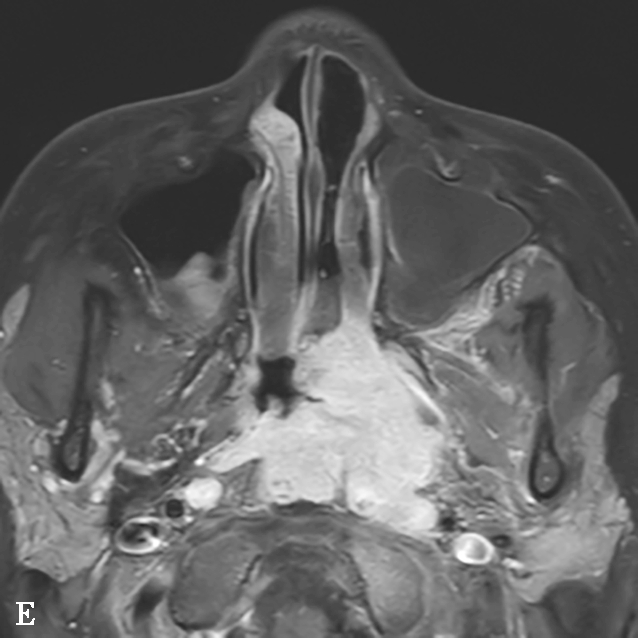

图1-2-5 青少年非角化型鼻咽癌

患者男,14岁,反复间断鼻出血、头晕头痛20余天。A.鼻窦CT横断面骨窗,示鼻咽顶后壁左侧软组织肿块,累及后鼻孔区,邻近左侧岩尖、蝶骨翼突骨质破坏、不完整,边缘毛糙;B.鼻窦CT冠状面重组骨窗,示左侧鼻咽顶后壁软组织肿块,邻近蝶骨翼突溶骨性骨质破坏,累及蝶骨体,边缘毛糙不整;C.鼻咽部MR T 2 WI横断面,示鼻咽左侧壁软组织肿块呈不均匀稍高信号,其间可见条状高信号,未见血管流空影;病变累及左侧翼内肌、窦后脂肪间隙;左侧上颌窦内可见积液呈明显高信号;D.鼻咽部MR T 1 WI横断面,示鼻咽部软组织肿块呈等信号,左侧上颌窦内积液呈低信号;E.鼻咽部MR T 1 WI横断面增强脂肪抑制序列,示鼻咽部病变呈明显强化,累及鼻咽左侧壁、顶后壁并跨越中线累及右侧咽隐窝,右侧咽后间隙淋巴结可见,与软组织肿块同步强化;F.鼻咽部MR T 1 WI冠状面增强脂肪抑制序列,示病变累及左侧咽旁间隙,左侧上颌神经明显增粗强化,并经上颌神经累及左侧海绵窦致其增厚、强化。活检病理符合鼻咽癌(非角化型)